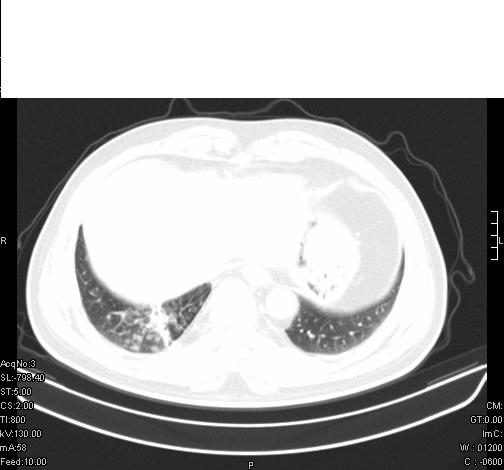

前几天,发了患者的平扫片,患者抗炎一周后增强扫描。右中叶病灶吸收明显,但下叶病灶未见明显吸收。右肺门可见结节影,看来凶多吉少

右肺下叶支气管管腔狭窄,管壁增厚,右下肺见斑片状高密度影,考虑右侧肺门中心肺癌伴阻塞性肺炎

右肺下叶散在的斑片状致密影,下叶支气管变窄。考虑:右肺慢性炎症。

右肺下叶支气管壁不规则增厚,右肺下叶有斑片状影分布。考虑右肺中央型肺癌伴右肺下叶阻塞性改变。建议支纤镜检查。平扫比增强较好显示了病变情况。

既然抗炎治疗有效,可继续治疗;右肺下叶支气管管腔狭窄,管壁增厚,右下肺见斑片状高密度影,右侧主支气管后见结节影(淋巴结?),肺癌不能排出。